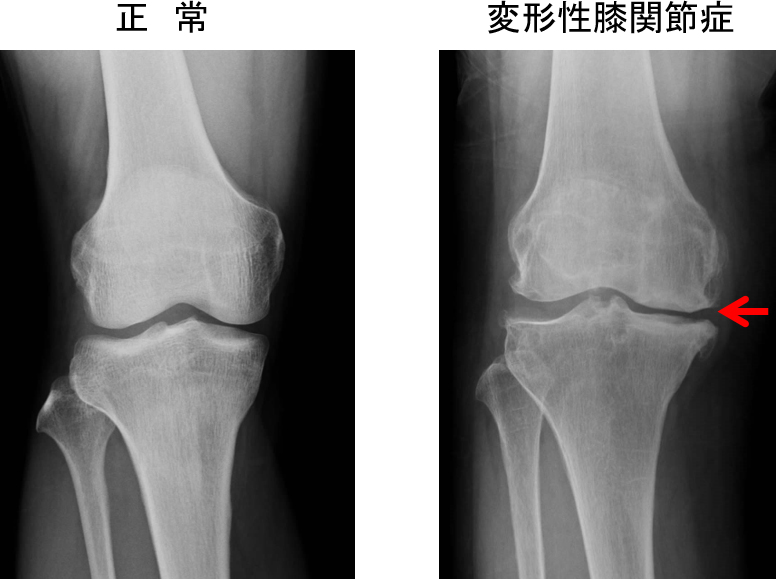

変形性膝関節症とは、「膝関節における骨の表面を覆っている関節軟骨が摩耗したために滑らかな関節運動が妨げられ、運動時痛・歩行時痛を生じる疾患」です。単純X線像では、関節裂隙の狭小化や骨棘などがみられます(図1)。変形性膝関節症になりやすい要因として、加齢(50歳以上)、女性、肥満、O脚、膝の酷使などが挙げられます。変形性膝関節症に対する治療として、保存療法と手術療法があります。保存療法には、教育、減量、歩行補助具、運動療法(中臀筋・大腿四頭筋強化訓練)、鎮痛薬(経口、貼付製剤)、ヒアルロン酸注射などがあり(図2)、保存療法に抵抗する場合には、手術療法を検討するため、慶友人工関節センターにコンサルトしています。